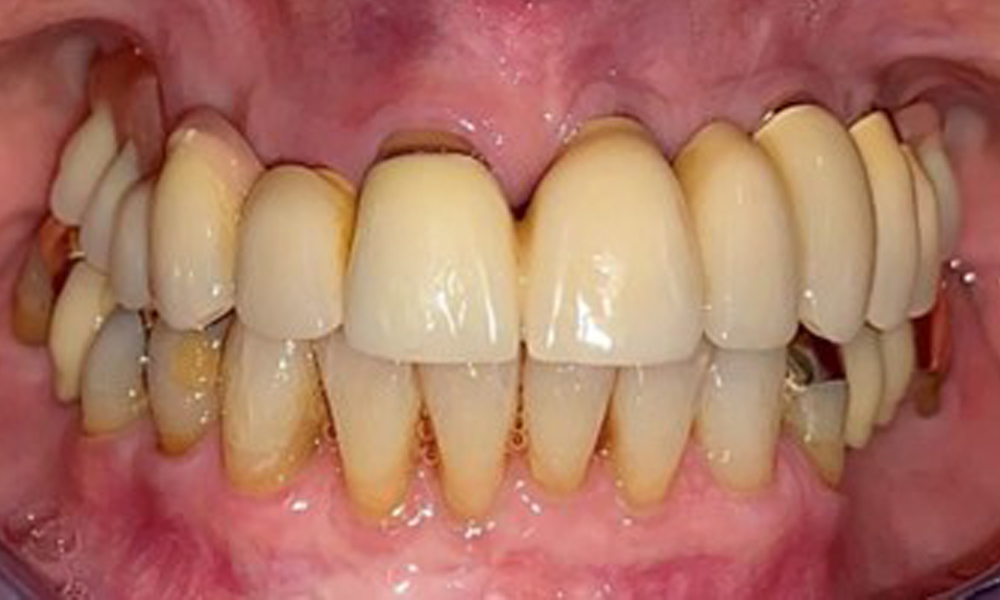

The patient was fitted with a combined removable maxillary telescopic prosthesis more than 25 years ago (Fig. 1, Fig. 2, Fig. 3) and is very happy with her dentures. The patient has an adequate fixed denture for the mandible (Fig. 4).

The dental findings are as follows: Combined removable implant and tooth-supported telescopic prostheses on implants 15, 13, 21, 23, 24, 25 and tooth 11 (Fig. 1, Fig. 2, Fig. 3). The patient was fitted with a fixed mandibular denture. Adequate bridges were present over 37 to 34 and 45 to 47 (Fig. 4), the crown margins were intact and there were no active caries. A composite filling with a marginal gap was present on tooth 43. There was mandibular gingival recession, exposing 1 to 3 mm of root surface. This also applies to 11.

Occlusal view of the mandible.

Fig. 4: Occlusal view of the mandible.

The radiological findings show partially edentulous dentition with maxillary implants for teeth 15, 13, 21, 23, 24, 25 and a telescopic crown on tooth 11. Adequate mandibular bridges spanning 37 to 34 and 45 to 47 are present. 48 is impacted. There are suspected secondary caries distally on 43 and mesially on 44. 44 is restored with a non-radiopaque cavity lining. There is generalised horizontal bone loss of approx. 10% to 30% and localised vertical bone loss affecting teeth 22 and 42 (Fig. 5).